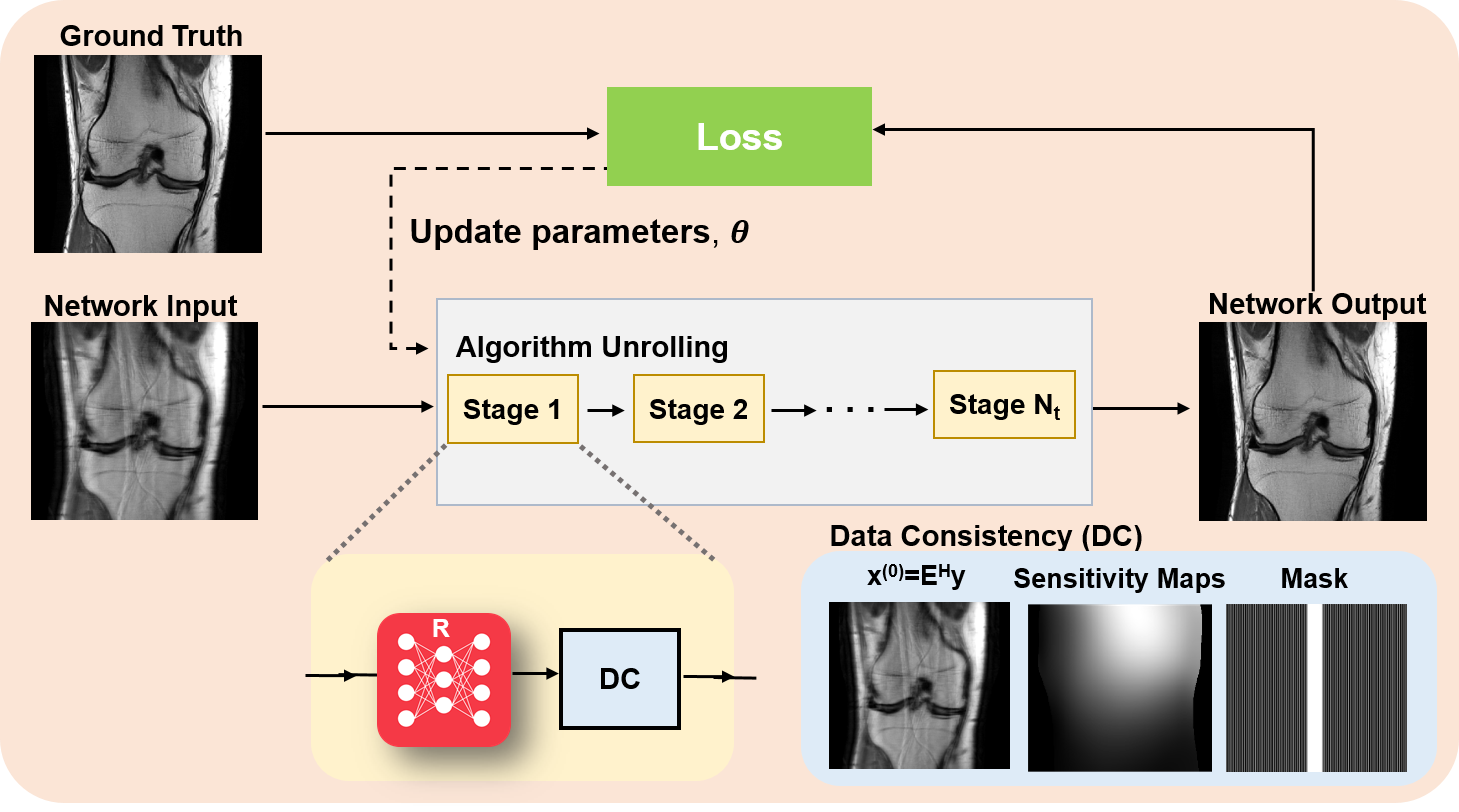

Algorithm unrolling considers the traditional iterative approaches considered in Section II-A and adapts them in a manner that is amenable to learning the optimal parameters for image reconstruction [21]. Traditional approaches require numerous iterations during optimization to solve the MRI reconstruction problem. Additionally, only a fixed, handcrafted regularizer is used, which do not necessarily model MR images accurately. Instead of solving a new optimization problem for each task, the whole iterative reconstruction procedure, including the image regularizer, can be learned. The original idea was proposed in the context of sparse coding [43], but has found great use in computational imaging applications, including computational MRI. In this line of work, a conventional iterative algorithm for solving Eq. (6) is unrolled and solved for a fixed number of iterations, as overviewed in Figure 3. The concept of algorithm unrolling will be introduced throughout this section. In practice, any iterative optimization algorithm can be unrolled for solving Eq. (6). In the context of MRI, algorithm unrolling is based on ADMM [44] as described in Eq. (9a)-(9c), gradient descent schemes [9], proximal gradient schemes [10, 45, 46], primal-dual methods [47, 48, 49], or variable splitting methods [50, 51, 52, 53]. Note that these algorithms contain a processing step associated with the regularization, such as the proximal operator as in Eq. (8b) or (9b), and a data consistency step that ensures the image estimate is consistent with the acquired k-space data, such as the gradient descent step in Eq. (8a) or the minimization step in (9a). We refer to this latter step that controls fidelity with the raw k-space data as data consistency layer (or block).

III-D1 Training unrolled networks

The output of the unrolled network depends on the variables in both the regularization network and data consistency layers, and can be represented with a function For the most generalized representation, we allow the regularizer CNN parameters and the data consistency parameters to vary across the unrolled iterations (cascaded stages). However, as noted earlier, the parameters can also be shared between stages. While for ease of notation, we have referred to the multi-coil operator as , this operator implicitly includes the sub-sampling mask . For the following, we will make this dependence explicit, and use and for the multi-coil operator and the measured k-space data, respectively.

The standard learning strategy for unrolled networks is to train them end-to-end, using the full network that has been unrolled for steps. For end-to-end training of unrolled networks, the most commonly used paradigm relies on supervised learning, where a database of fully-sampled measurements/ground-truth images as a reference. Given a database of pairs of input and reference data, the supervised learning loss function can be written as

| (27) |

where represents the network parameters, is the number of samples in the training database, is a loss function characterizing the difference between network output and referenced data, denotes the ground-truth image for subject . The domain for the loss function can be image, k-space or a mixture of them. Numerous loss functions such as , , adversarial and perceptual losses have been used in supervised deep learning approaches [11].